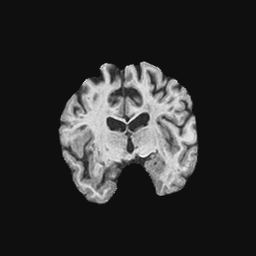

Exp. 1: Segmented adult brain data is used to evaluate our network’s regression performance with known ground truth . 85 brains from the ADNI data set[1] were randomly selected; 70 brains for and 15 brains for . Fig. 2 shows an example slice of the ground truth and the reconstructed .

Each brain has been centered and re-sampled in a volume. Using the Fibonacci Sphere Sampling method, a density of 500 unique normals is chosen with 64 sampling planes spaced evenly apart on the Z-axis (giving a spacing of 4mm). This therefore yields a maximum of 32000 images per brain; 2.24M for the entire training set and 345K for the entire validation set. After pruning with little or no content, this figure drops to approximately 1.2M images for training and 254K for validation. Training took approximately 27hrs for 30 epochs.

Reconstructing from initialisation without SVR yields a PSNR of 23.7 1.09; with subsequent SVR the PSNR increases to 29.52.43 when tested on 15 randomly selected test volumes after four iterations of SVR.

0..5 Randomly selected illustrative inference results

Here we show for Exp. 1, Exp. 2, and Exp. 3 randomly selected examples of images that have been presented to the network (ground truth) compared to an image sampled at the predicted location.

In these experiments, we present a ground truth (GT) image to the network to estimate the respective transformation parameters needed to reorient the slice in its correct world co-ordinates. Using the transformation parameters, we generated a slice from the 3D atlas in the location where the network has predicted that slice should be (denoted as SVRNet).

The slices are compared side-by-side to give a visual representation of “where the slice really is” and “where the network thinks the slice is”.

0..5.1 Exp. 1:

Slices, extracted from a correctly registered and reconstructed 3D volume, from the testing data set are presented to the network. The predicted slice is extracted from the same volume, using parameters estimated by SVRNet as shown in Fig. 8 and 9.